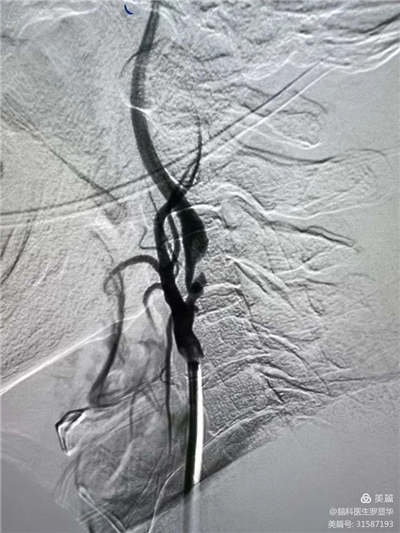

李東波副院長團(tuán)隊正在為患者行頸動脈支架植入術(shù)

手術(shù)過程:指引導(dǎo)管到位

手術(shù)過程:球囊擴(kuò)張后,protege支架到位

術(shù)后造影示狹窄解除